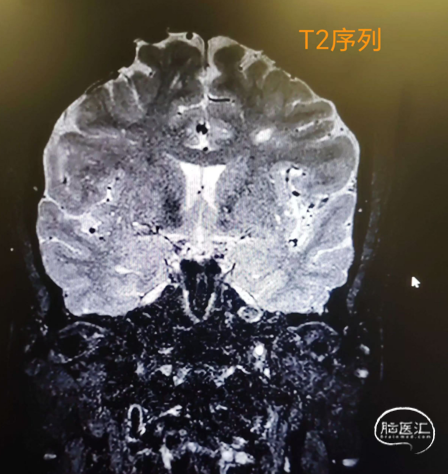

入院颈内动脉颅内段高分辨核磁(2024-09-11)。

入院颈内动脉颅内段高分辨核磁(2024-09-12)。